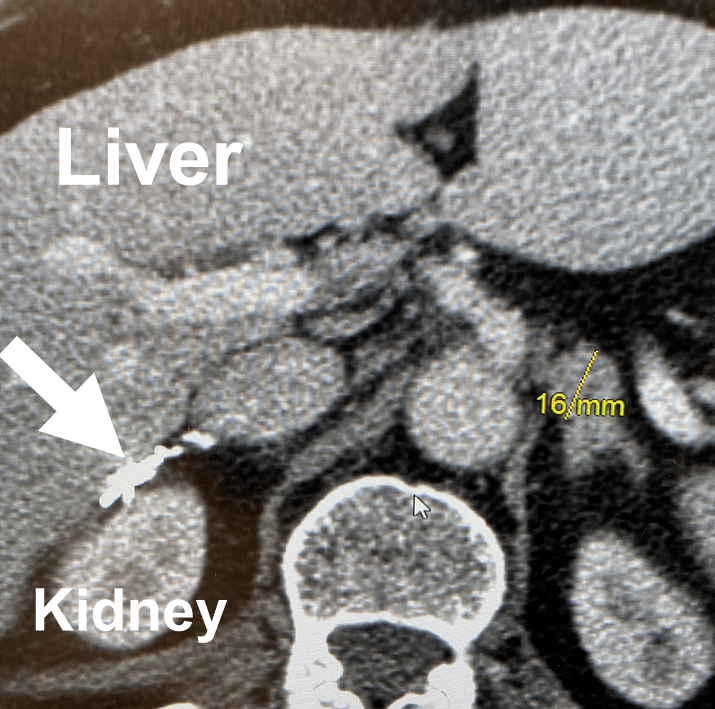

Adrenal Glands MRI Boulder MRI Adrenal Gland Removal Operation adrenalectomy is the surgical removal of one or both adrenal glands. Adrenal glands are small glands located on top of both kidneys. adrenal center surgeons remove the vast majority of adrenal tumors laparoscopically. a laparoscopic adrenalectomy is a minimally invasive procedure that uses small incisions and tools to access the adrenal gland. the main treatment for. Adrenal Gland Removal Operation.